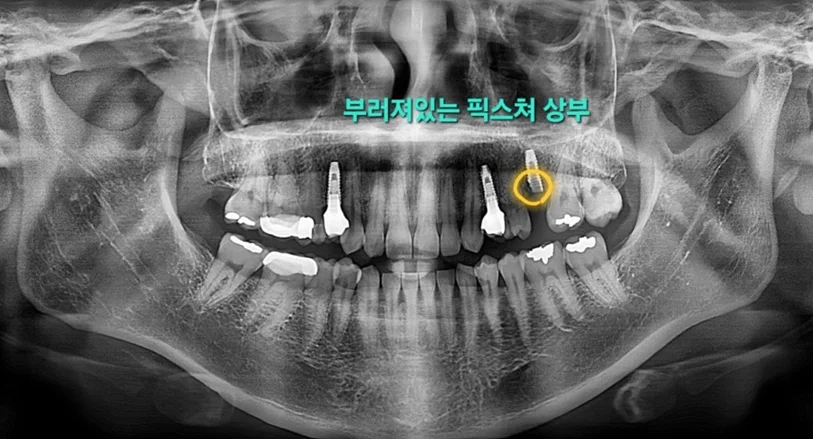

육안으로 확인했을 때 크라운이 빠진 상태였고, 파노라마 엑스레이 상에서 임플란트 픽스쳐 상단 부분이 찢어져 부러진 것이 명확히 보였습니다.

▲ 파노라마 엑스레이: 픽스쳐 상단 파절 확인

해당 부위는 저작력이 가장 강한 제1대구치 부위였고, 식립된 픽스쳐의 직경은 4.0mm였습니다. 저작압력이 높은 대구치 부위에 상대적으로 가는 직경의 픽스쳐가 들어간 것이 파절의 주요 원인으로 판단되었습니다.